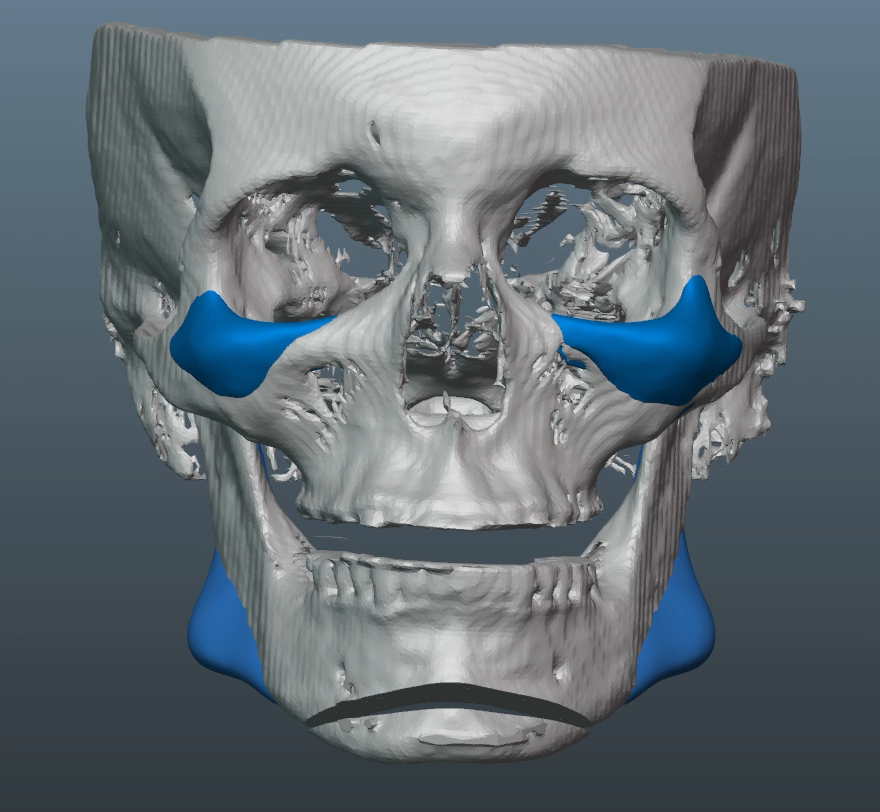

Recieved the draft 1 of the design, what changes should i ask for?? a couple of things i can think of are malar implants not giving enough lateral protrusion, gonion flaring.

I also am planning to include infra implants as well.